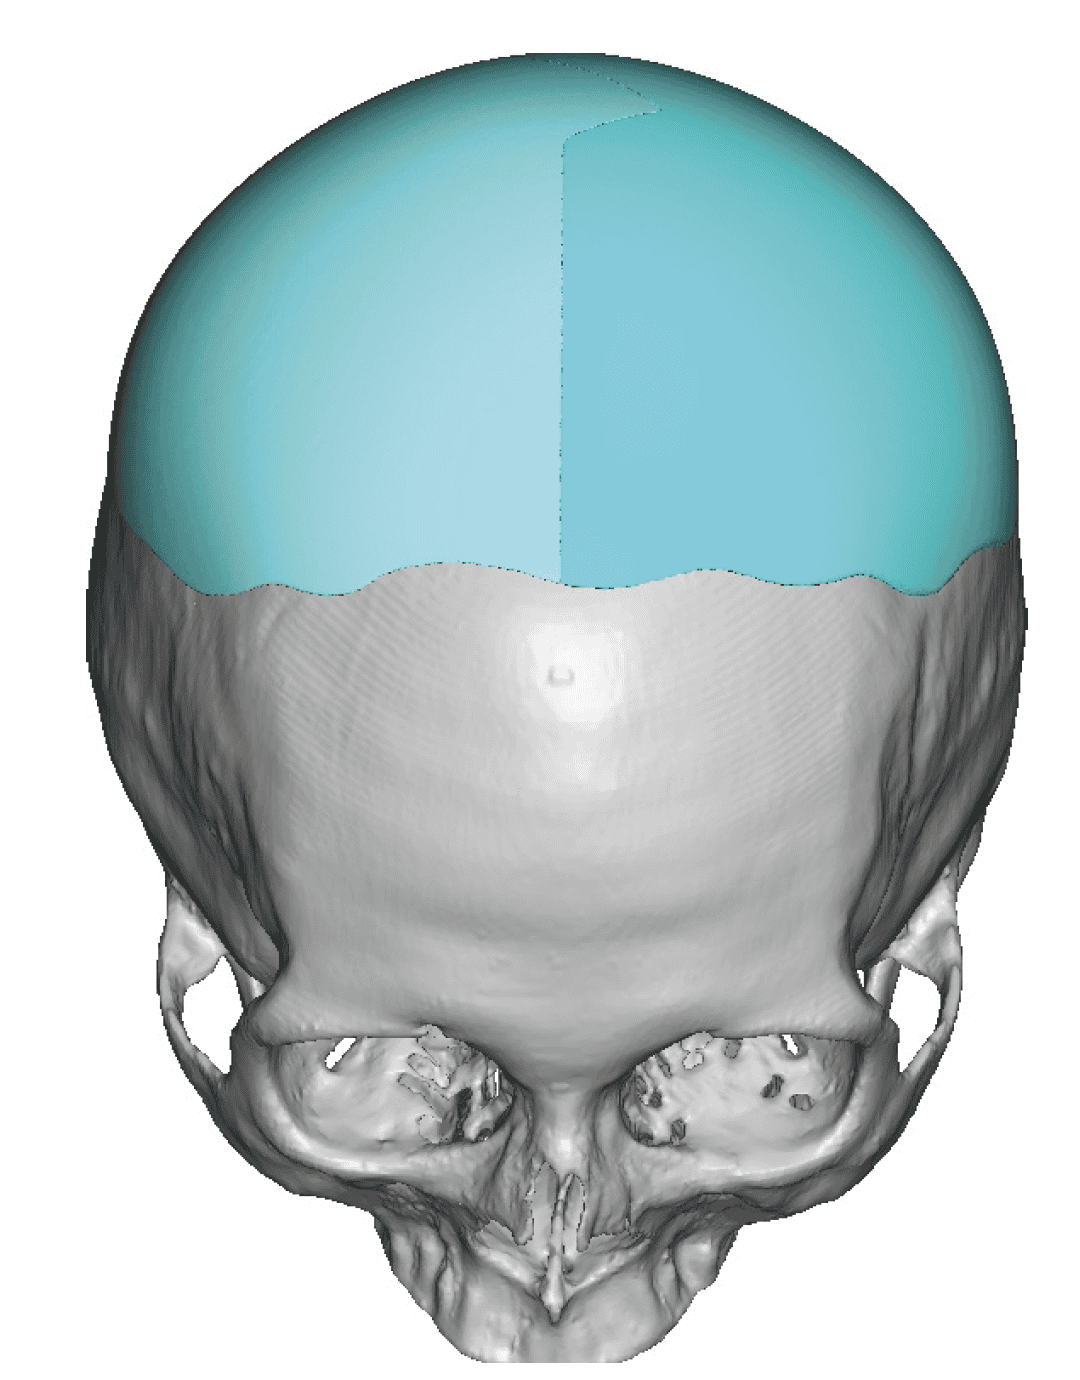

Patient 28

Desire for rounder shape to the top of the head from a congenital parasagittal deficiency skull shape.

Custom skull implant designed to fill in the parasagittal deficiencies.

Desire for rounder shape to the top of the head from a congenital parasagittal deficiency skull shape.

Custom skull implant designed to fill in the parasagittal deficiencies.